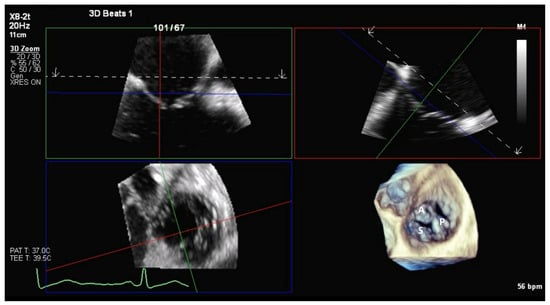

6.1. TEE-Guided Tricuspid TEER